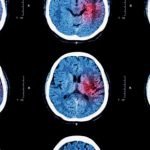

avc